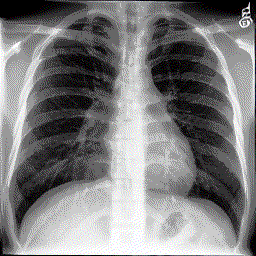

Animated GIF to illustrate BiomedJourney capability. Given a previous radiology image and text instruction, BiomedJourney generates a new counterfactual radiology image.

BiomedJourney generate counterfactual medical images. (Left) The evolution dynamics of the generated medical images using BiomedJourney. (Right) Interactive emulation of progression of pleural effusion.

Starting from a patient's real Chest X-ray image, our BiomedJourney model can precisely follow the progression instructions to generate outcome images.

From the patient's prior image to the BiomedJourney image, see them side by side.